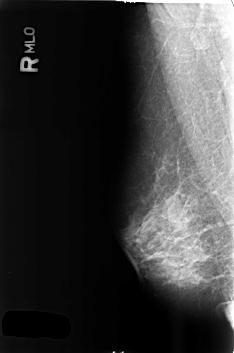

B_3374_1.RIGHT_MLO

RIGHT_MLO LINES 4584 PIXELS_PER_LINE 3040 BITS_PER_PIXEL 12 RESOLUTION 50 NON_OVERLAY